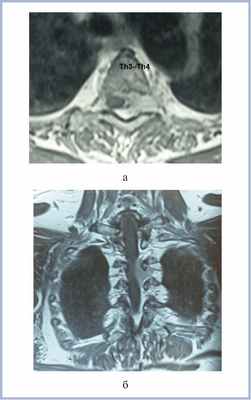

Пациентка В., 66 лет, поступила в клинику с жалобами на боли в межлопаточной области, усиливающиеся при физической нагрузке. Интенсивность боли оценивала в 6—7 баллов по визуально-аналоговой шкале (ВАШ). Боль в межлопаточной области беспокоит в течение 14 лет. При МРТ выявлено экстрамедуллярное объемное образование на уровне Th3—Th4 позвонков слева, с экстра- и интрадуральным компонентом, распространяющееся в межпозвонковое отверстие Th3—Th4 (рис. 1).

Рис. 1. МР-томограммы (Т1-ВИ с контрастным усилением) пациентки с менингиомой на уровне Th3—Th4 позвонков перед операцией в аксиальной (а) и фронтальной (б) проекциях. Определяется объемное образование (менингиома) на уровне Th3—Th4 позвонков, распространяющееся в межпозвонковое отверстие.

Пациентка неврологически интактна, оценка по шкале Klekamp—Samii [6] — 24 балла (4 балла по показателю «чувствительные нарушения или боль», 5 баллов по остальным показателям).